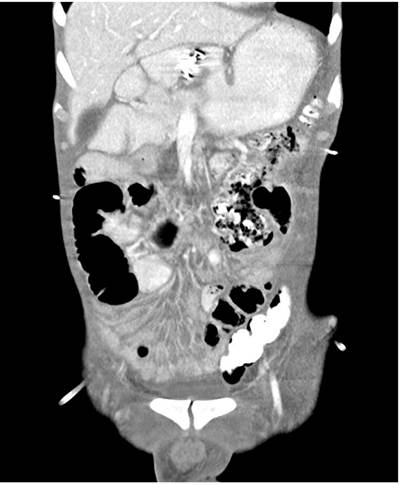

By the fifth postoperative day, there was clinical deterioration due to febrile episodes, abdominal pain, and tachycardia, so a new abdominal tomography was performed, reporting an intra-abdominal collection in the left flank of 12 x 12 x 5 cm secondary to the jejunal fistulous process (Figure 2).

On the fifth day after the endoscopic procedure, an imaging follow-up of the digestive tract confirmed no pyloric continuity with adequate patency of the gastrojejunostomy. A contrasted abdominal tomography showed a decrease in the intra-abdominal collection without contrast medium extravasation (Figures 4 and 5).